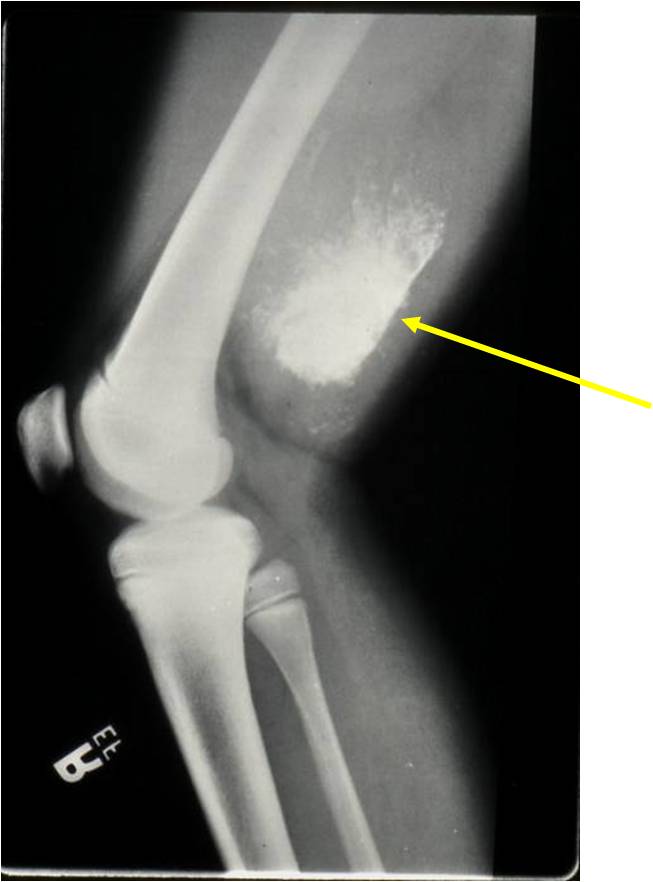

Radiographic Presentation

- Aggressive motheaten to permeative lesion

- Indistinct border in most cases

- Osseous destruction with a soft tissue component

- Chondroid matrix calcification may be present (60-70% of cases)

- Soft tissue mass

(Right Arrow) Cartilaginous Component